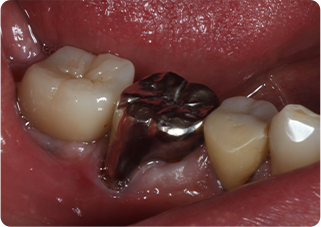

セラミックアンレー症例①

術前

むし歯除去

ラバーダム防湿

術後

| 主訴 | むし歯の治療をしたい |

| 治療期間/回数 | 2週間、2回 |

| 価格(税込) | 77,000円(税込) |

| リスク・副作用 | セラミックの破損、一時的な知覚過敏が生じる場合がある |

| ポイント | ラバーダム防湿をし、唾液や呼気の侵入を防ぎ湿度を下げることで、セラミックの接着力の向上を計った。接着力の向上により、脱離や破折の予防になる。 |